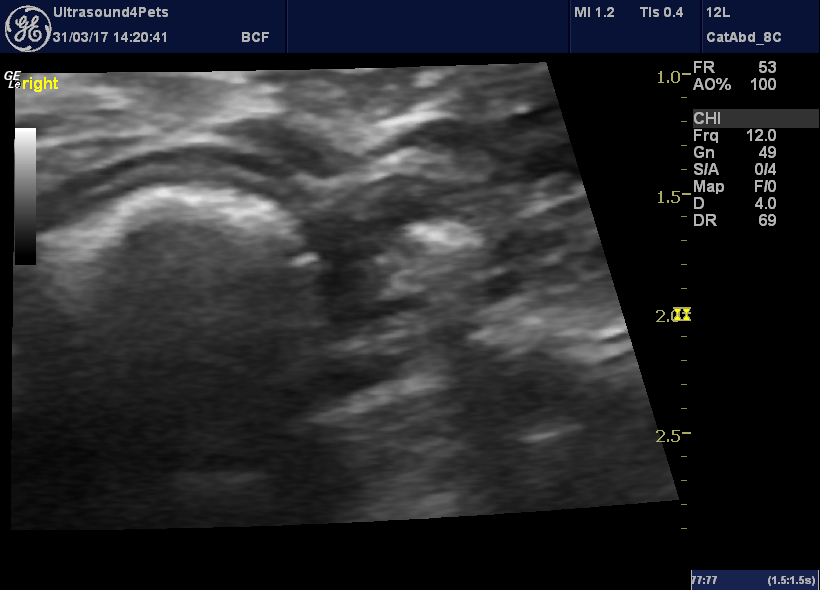

From www.vetpracticesupport.com

Hair balls a sonographic challenge Vet Practice Support Hairball In Calves hairballs are often found on postmortem in calves with ulcers but they are found in a similar number in calves without ulcers. the dairy farm located at samrang under bhutan livestock development corporation limited had. some of the foreign items commonly found inside cows are hairballs. The calves died with distinct symptoms such as high respiration,. . Hairball In Calves.